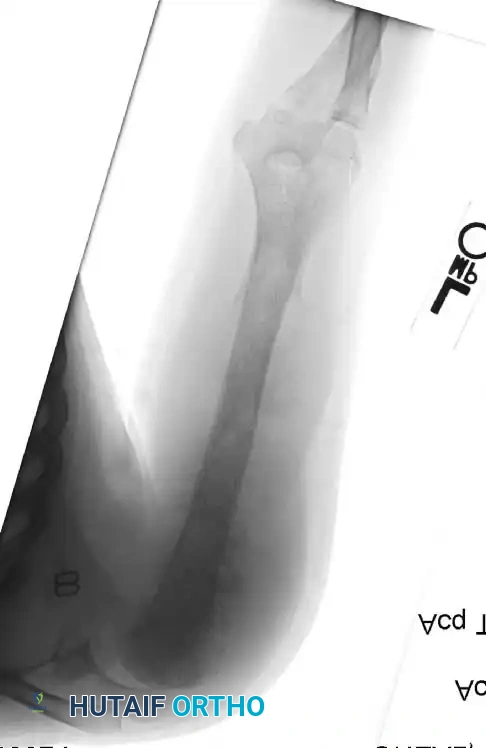

Postoperative radiograph demonstrating a complex modular endoprosthetic reconstruction of the humerus and elbow joint following wide resection.